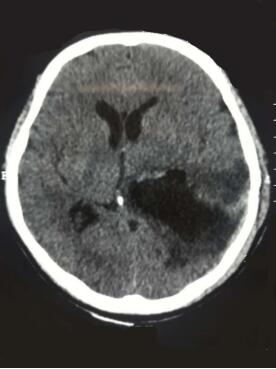

术前头颅CT影像,红圆圈标注即为脑膜瘤,直径有5厘米。

术后头颅CT影像显示脑膜瘤被切除